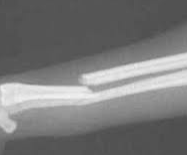

骨折(Fracture) ~ 骨折の原因について

骨折は、骨の堅牢性(hardness)と弾力性(elasticity)の限界をこえる力が作用しておこる骨の損傷で、骨の完全もしくは不完全な離断です。外力に対する骨の抵抗力は、家畜の種類、用役、年齢、骨の種類と部位、骨の疾患・栄養障害の有無な...